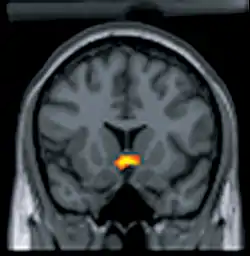

مكافأة تنبيه الدماغ (BSR) هي ظاهرة ممتعة تنتج عن تنبيه مباشر لمناطق محددة من الدماغ، اكتُشفت من قبل جيمس أولدز وبيتر ميلنر. تعمل مكافأة تنبيه الدماغ كإشراط استثابي قوي معزِّز. ينشِّط التنبيه دورة نظام المكافأة ويؤسس عاداتِ استجابةٍ مماثلة لتلك المؤسسة بواسطة المكافآت الطبيعية مثل الطعام والجنس.[2] بينت تجارب على مكافأة تنبيه الدماغ أن تنبيه تحت المهاد الجانبي، جنبا إلى جنب مع مناطق أخرى في الدماغ مرتبطةٍ بالمكافأة الطبيعية، كان مكافئا ومحدثا للتحفيز كذلك.[3] يُنتِج التنبيه الكهربائي للدماغ وحقن العقاقير داخل الجمجمة إحساسَ مكافأةٍ قويٍ بسبب تنشيط مباشر نسبيا لدورة نظام المكافأة، ويعتبر هذا التنشيط مباشرا أكثر من المكافآت الناتجة عن منبهات طبيعية، لكون إشارات تلك المنبهات تنتقل عبر أعصاب محيطية غير مباشرة بشكل أكبر.[4] وُجدت مكافأة تنبيه الدماغ لدى جميع الفقاريات التي تم اختبارها بما في ذلك البشر، وثم إثبات أنها وسيلة مفيدة لفهم كيفية معالجة المكافآت الطبيعة بواسطة مناطق ودورات محددة في الدماغ، وكذلك لفهم النقل العصبي المرتبط مع نظام المكافأة.[5]

التنبيه الذاتي داخل القحف (ICSS) هي طريقةُ الإشراط الاستثابي المستخدَمةُ لإنتاج مكافأة تنبيه الدماغ في الوضع التجريبي. يتطلب التنبيه الذاتي داخل القحف أفرادا مزروعة فيهم إلكترودات بشكل دائم في مناطق متعددة من الدماغ معروف بأنها تُحدث مكافأة تنبيه الدماغ حين يتم تنبيهها، ويُدرّب هؤلاء الأفراد للاستجابة المستمرة للتنبيه الكهربائي لتلك المناطق من الدماغ.[6] دراسات التنبيه الذاتي داخل القحف مفيدة بشكل خاص لاختبار تأثيرات مختلف التلاعبات الدوائية على حساسية نظام المكافأة، ويتم استخدام التنبيه الذاتي داخل القحف كوسيلة لقياس مدى مسؤولية ومساهمة العقارات بمختلف أقسامها في الإدمان بما في ذلك تلك التي تعمل كأحادي أمين الفعل، أشباه أفيونيات، والنواقل العصبية كولينية الفعل. بيانات هذه الدراسات تتناسب مع نتائج دراسات التعاطي الذاتي حول خصائص العقار المسببة للإدمان.[7]